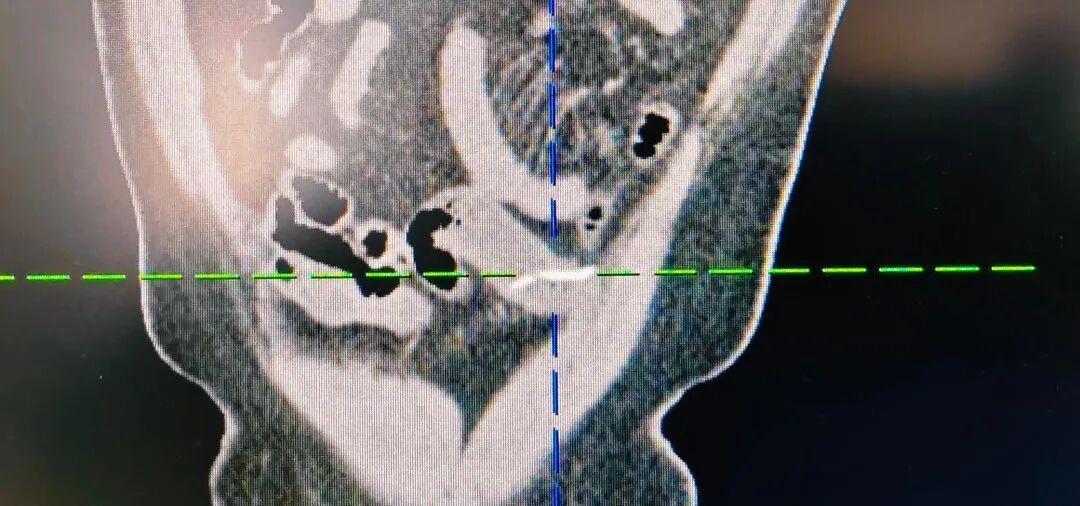

经漳州第三医院普外二科团队详细检查,最终确诊为小肠异物穿孔,而闯下弥天大祸的,竟然是一根不起眼、只有两三公分长的小鱼刺,普外二科团队为患者行“腹腔镜下小肠破裂修补+异物取出术”。

就算侥幸过了食道,到了肠胃里,尖刺也可能划伤肠胃黏膜,甚至直接扎穿胃、小肠、大肠,造成穿孔。

一旦穿孔,胃里的胃酸、小肠里的消化液和食物残渣、大肠里的粪便和大量细菌,会全部漏进腹腔,引发严重腹膜炎,出现剧烈腹痛、高烧、肚子僵硬如石板。